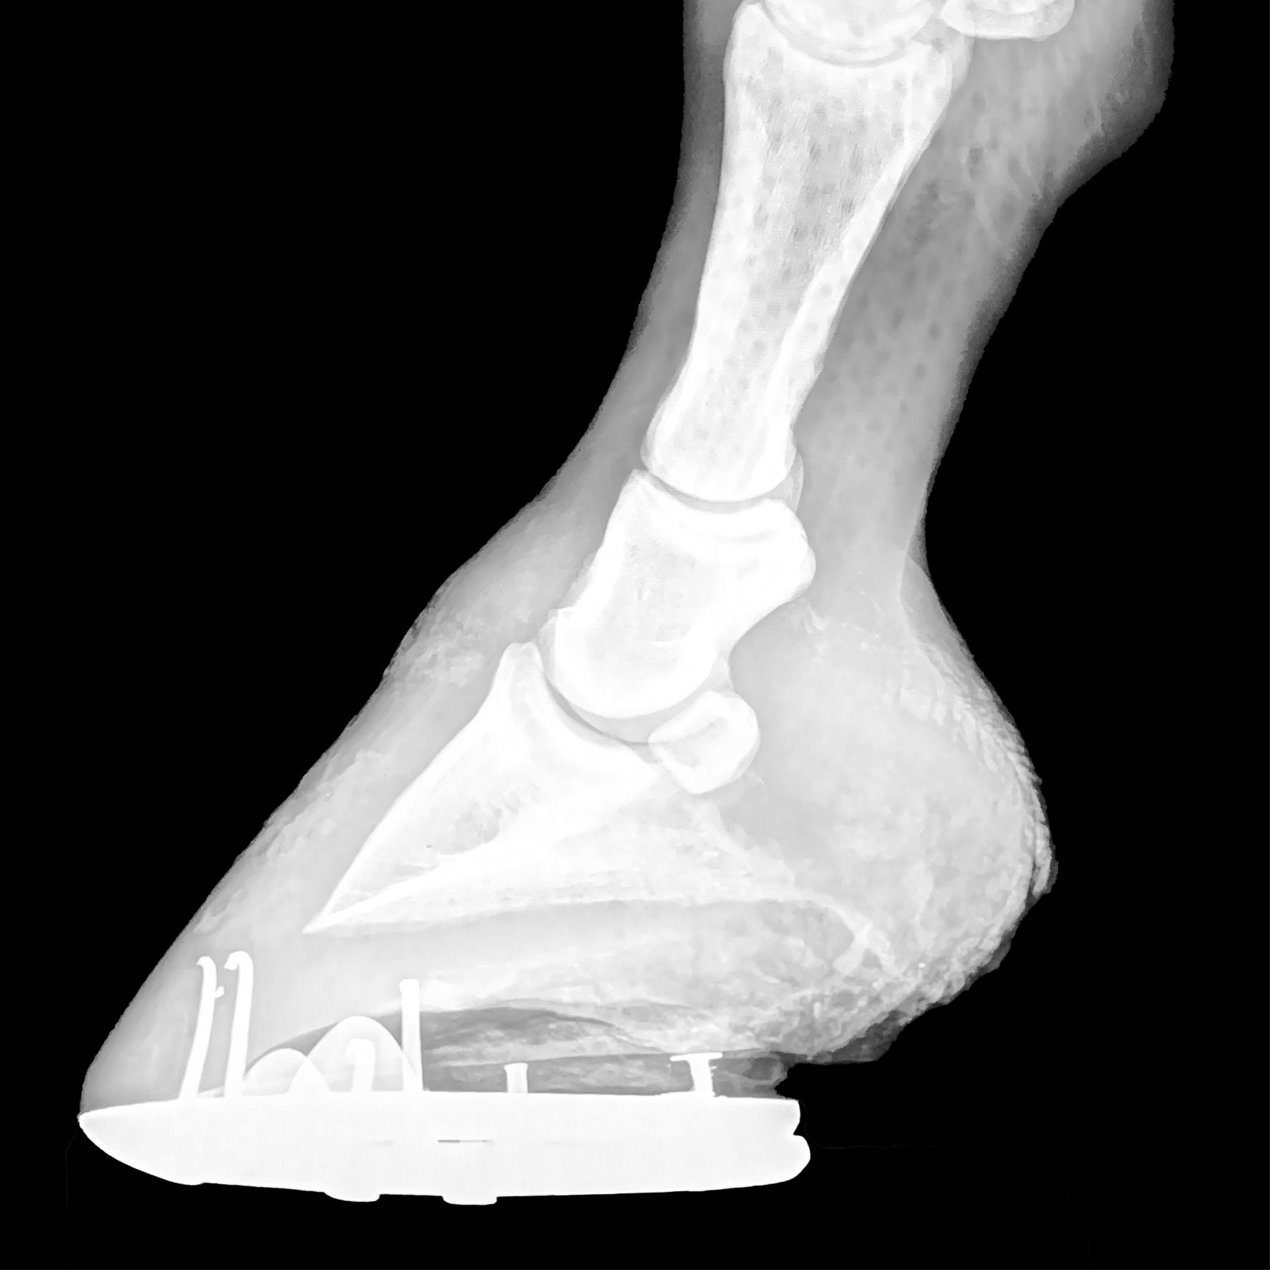

Excessive Distance Between the Coffin Bone and Ground Surface